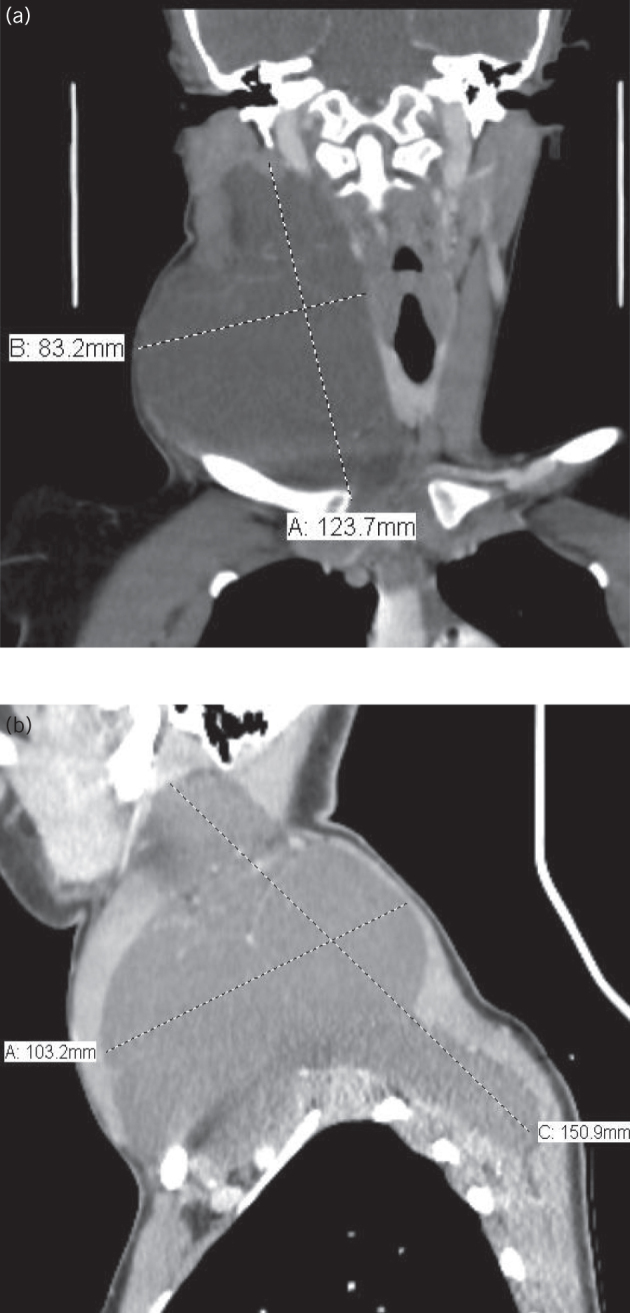

Contrast enhanced computed tomography of the neck and chest showed a 15 × 10 × 8 cm multiloculated cystic lesion of near water density occupying both right anterior and posterior triangles of the neck, which caused a mass effect over right sternocleidomastoid muscle, carotid artery, internal jugular vein, larygopharynx and trachea (Fig 3). There was no evidence of lung lesion causing lymphatic obstruction. The picture was highly suggestive of cystic hygroma. Thus, after informed consent had been taken, we proceeded for total surgical excision (Fig 4).

Figure 3.

Contrast-enhanced computed tomography of the neck shows the approximate dimensions of the cystic hygroma; a) coronal view; b) sagittal view.